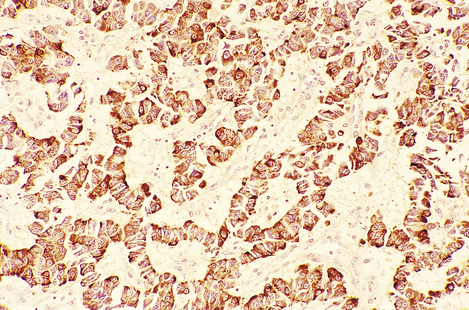

Modern histological classification of the types of hormone-secreting cell is based on immunohistochemistry, a technique in which antibodies raised to a hormone bind to the cells containing that hormone in tissue sections, leading to a coloured stain (Fig. 17.4). This has enabled the true hormone content of the cells to be determined, and has rendered obsolete the traditional classification of the cells into eosinophil, basophil and chromophobe types according to their staining by haematoxylin and eosin (H&E). By electron microscopy, the cells of the adenohypophysis are seen to contain electron-dense granules ranging from 50 to 500 nm in diameter (Fig. 17.5); these contain stored secretory products. The six types of hormone-secreting cell are shown in Table 17.1.

image

Fig. 17.4 Growth hormone-containing cells in an adenoma of the adenohypophysis. Immunoperoxidase localisation of growth hormone. Cells containing growth hormone are stained brown by this technique.